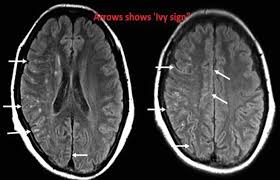

모야모야병은 뇌 기저부에 있는 주요 혈관이 점차 좁아지면서 뇌로 가는 혈류량이 줄어드는 질환입니다. 혈류가 부족해지면 뇌는 새로 가늘고 약한 혈관을 만들어 혈류를 보완하려고 하는데, 이 혈관들이 모여 있는 모습이 연기처럼 보여 ‘모야모야’라는 이름이 붙었습니다.

● 뇌출혈

특히 성인 환자에게서 자주 나타나는 심각한 증상입니다.

- 벼락처럼 갑작스러운 두통